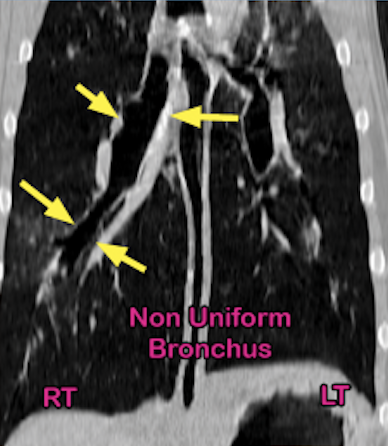

6-year-old American Bulldog with left-sided, muffled lung sounds received thorax CT scan to determine the cause.